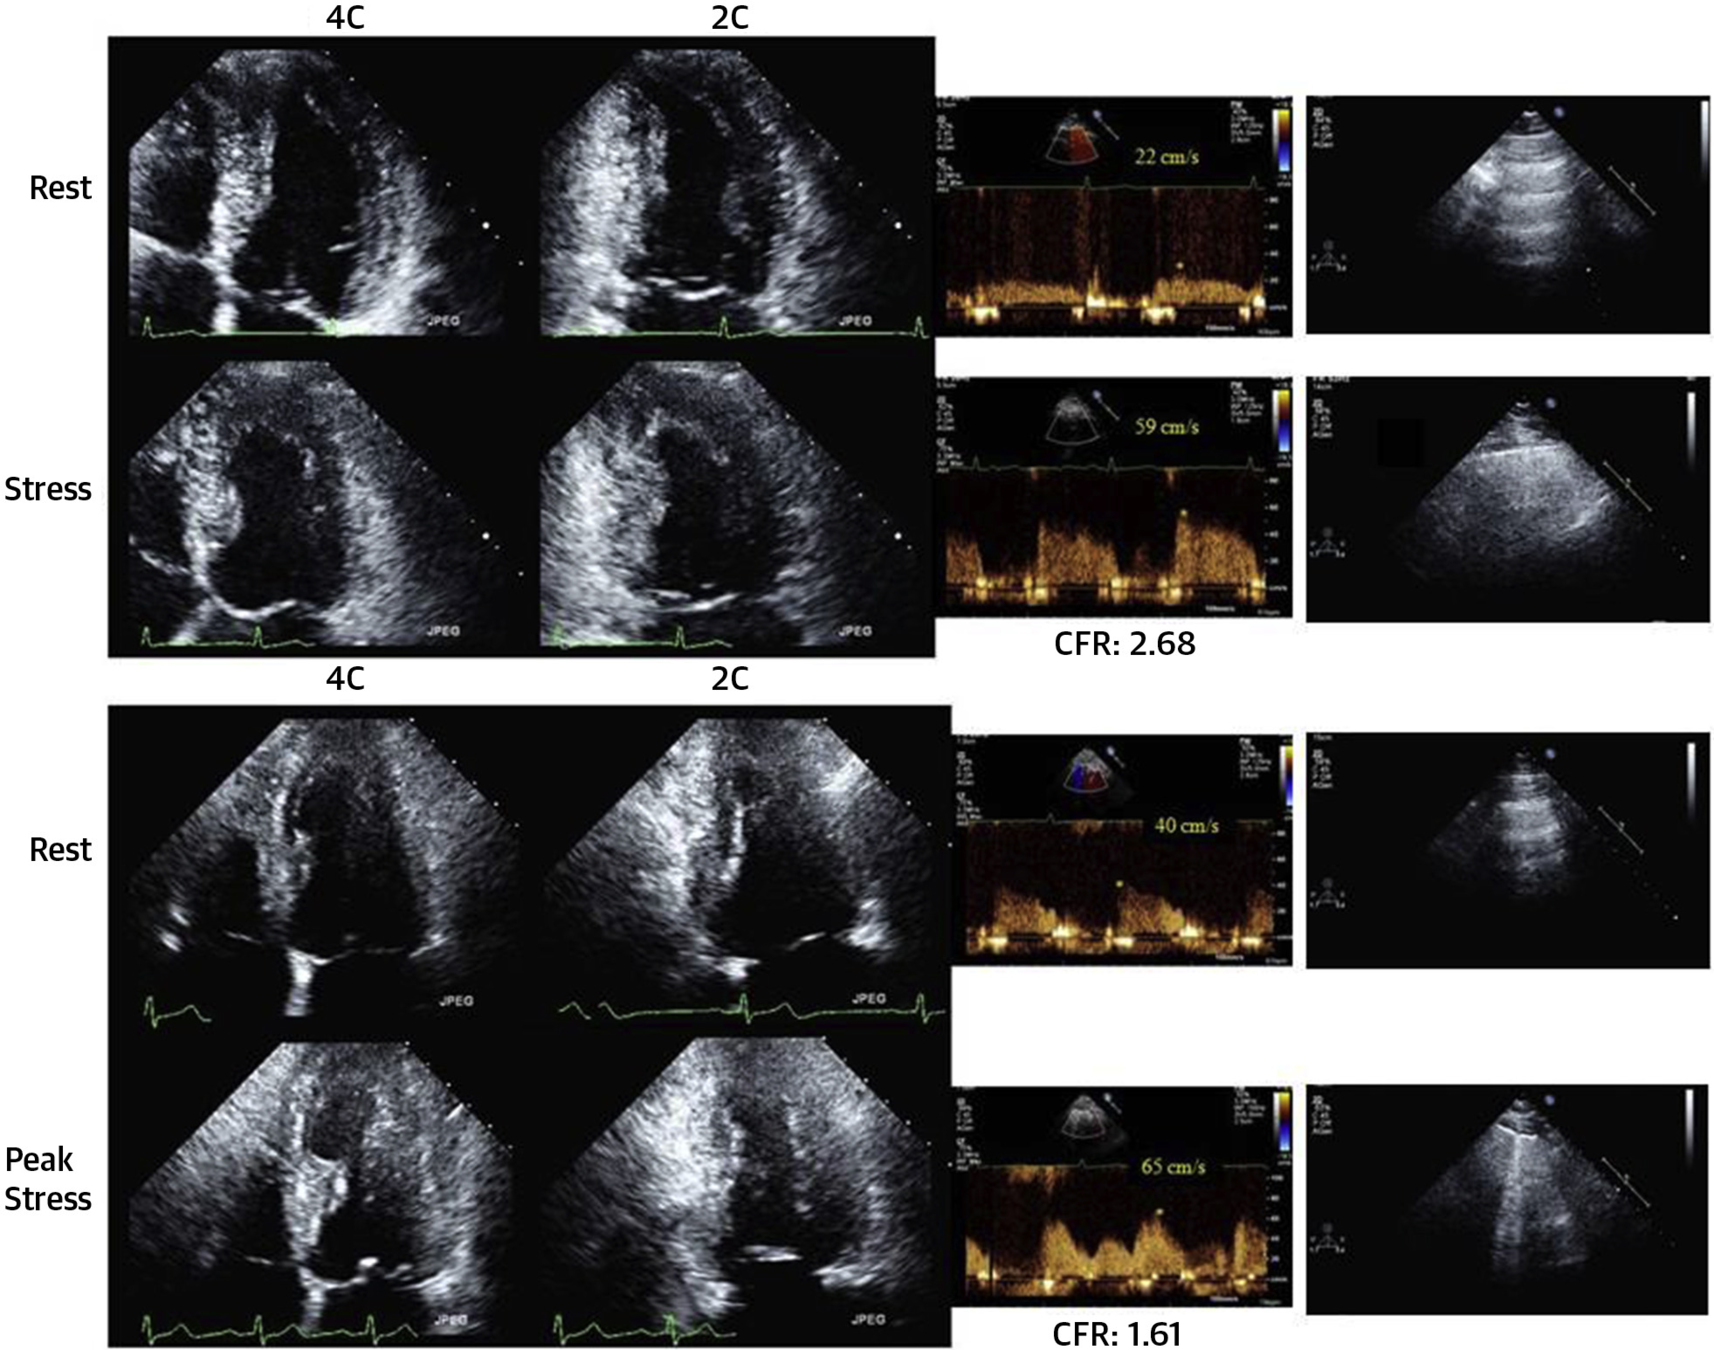

Step D: CFVR

• Assessment: Coronary flow velocity reserve of mid-distal LAD

• Positivity: CFVR < 2

• Success rate of 88% in obtaining CFVR on LAD (3000/3410)

• 80% with exercise (bike) and 81% with dobutamine

•  Acquisition and Interpretation in < 4 minutes

• Assesses both epicardial CAD and coronary microcirculation

• Dopplers obtained and reviewed offline

• *Note: Stress Echo 2030 protocol, pharm SE or if exercise, then given adenosine bolus at end of recovery to assess CFVR

• Acquisition: modified low parasternal and apical views

• Studies agree, onerous, but with training it is possible